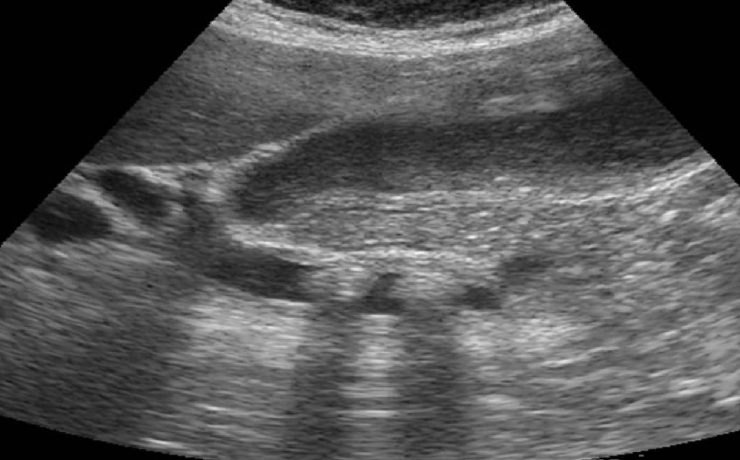

Hipertrofia prostatica benigna

Enfermedad común afecta hombres de edad avanzada A) Sintomatología en relación: Retención aguda de orina y síntomas del tracto inferior (hematuria, infección de tracto urinario) B) Examen digital rectal forma parte de la evaluación (pero es limitada su utilidad) El diagnóstico correcto es importante: Ultrasonido Transabdominal (más útil y